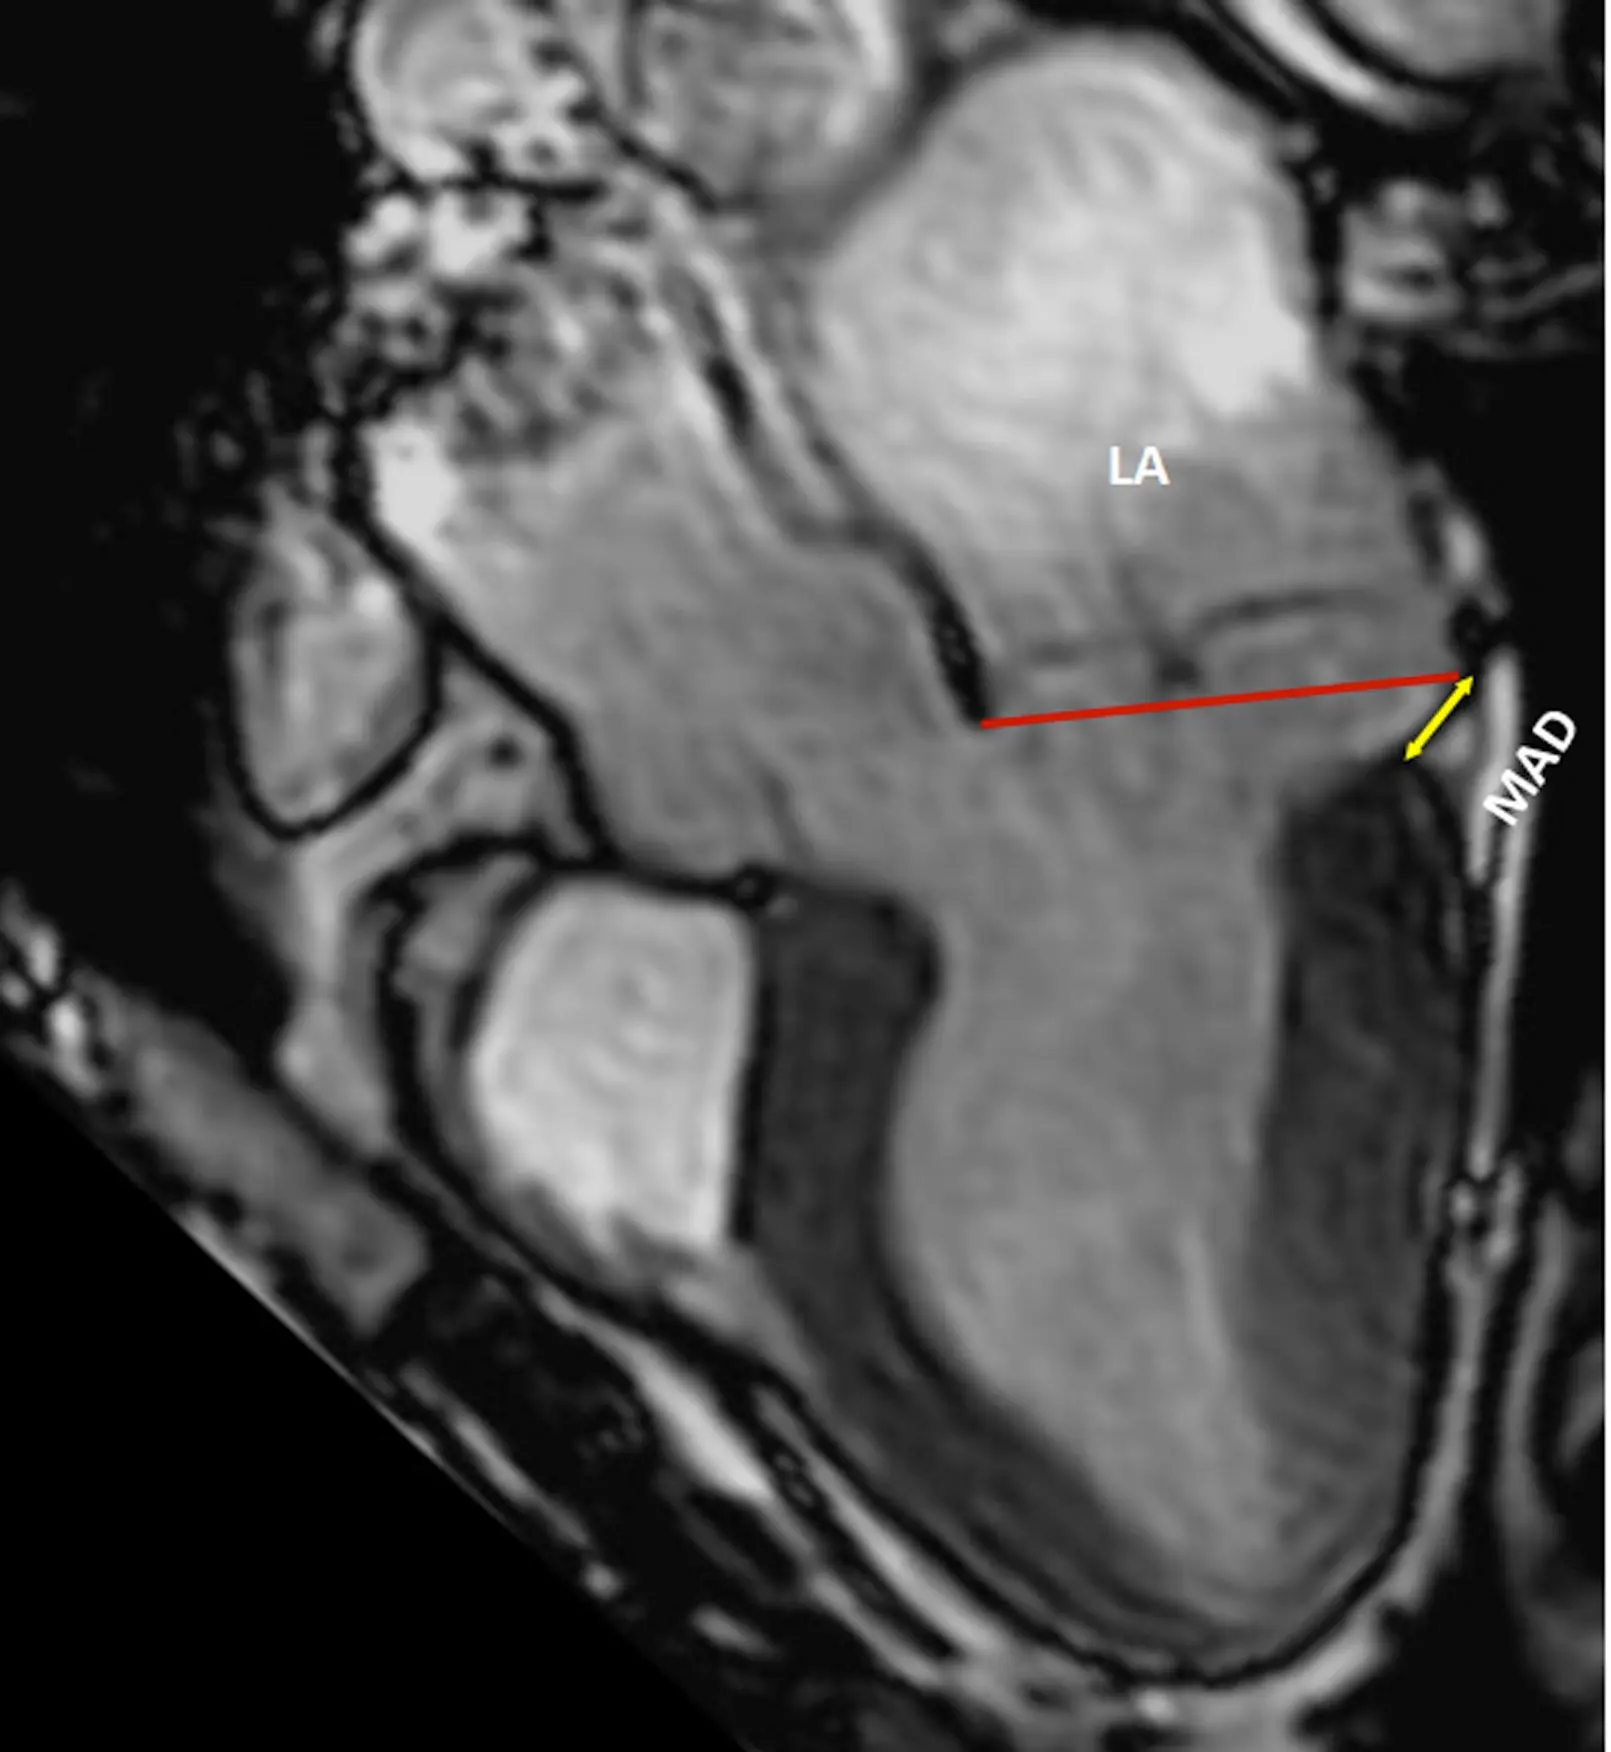

• MAD length is measured in the parasternal long axis view (or equivalent sagittal views on CMR), from the insertion of the posterior leaflet on the detached mitral annulus to the border of the bulging LV myocardium.

Figure source: 1. CMR long-axis view in end-systole displaying mitral valve prolapse with MAD (yellow arrow). The red line indicates the plane of the mitral annulus.